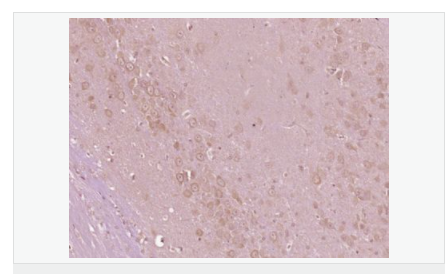

| 產品應用 | ELISA=1:5000-10000 IHC-P=1:100-500 IHC-F=1:100-500 IF=1:100-500 (石蠟切片需做抗原修復) not yet tested in other applications. optimal dilutions/concentrations should be determined by the end user. |

交叉反應:Mouse,Rat(predicted:Human,Dog,Pig,Horse,Rabbit) 推薦應用:IHC-P,IHC-F,IF,ELISA